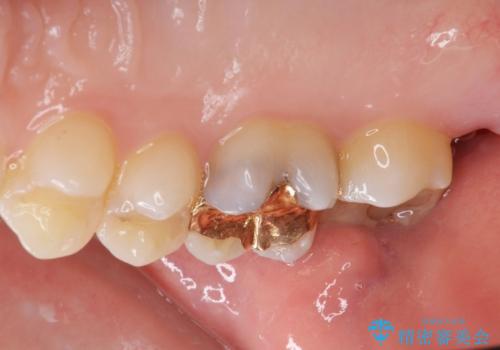

- 金の詰め物の中が黒く透けていて虫歯があるので拡大鏡下で外し、虫歯がない事を確認した後、被せ物で治療しました。

一番奥の歯は古い樹脂の治療の後がありましたのでセラミックの詰め物で治療しました。

- ジルコニアクラウンスタンダード・仮歯 12.1万円 e-maxインレー 7.7万円費用は治療当時の料金となります